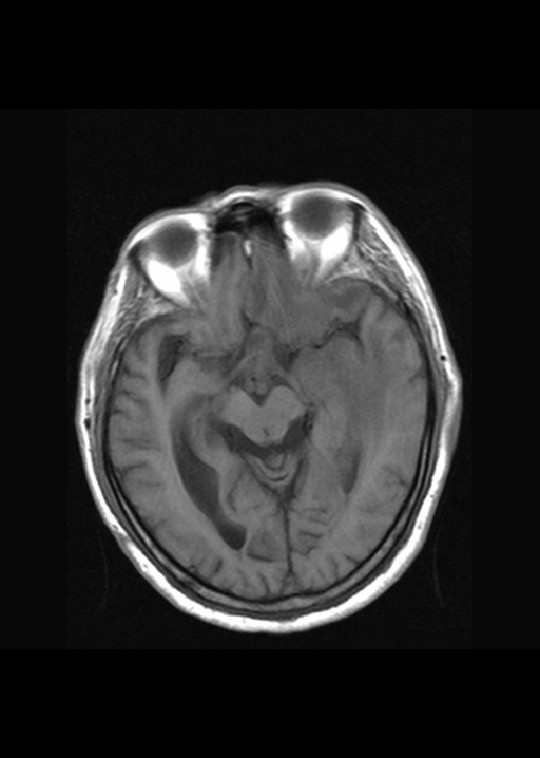

(左额颞叶)非霍奇金淋巴瘤,b细胞性,弥漫性大b细胞型。免疫组化结果:cd45(lca) +,vimentin +,ck(ae1/ae3) -,ema -,cd3 -,cd20 +++,cd30 -,plap -,cd79a +,gfap -,alk -,s-100 -。

左侧基底节区异常强化信号,考虑胶质瘤。

基底节区团块样强化,淋巴瘤。

左侧基底节区病灶t1wi呈不均匀稍低信号,t2wi呈稍高信号,周围伴有水肿。增强扫描呈均匀团块样或者抱拳样明显强化,相邻的柔脑膜亦见线样强化。首先考虑淋巴瘤。可惜没有ct平扫,如果ct平扫病灶呈高密度,那么更支持pcnsl的诊断。

病理结果:(左额颞叶)非霍奇金淋巴瘤,b细胞性,弥漫性大b细胞型。免疫组化结果:cd45(lca) +,vimentin +,ck(ae1/ae3) -,ema -,cd3 -,cd20 +++,cd30 -,plap -,cd79a +,gfap -,alk -,s-100 -。

左侧基底节区病灶t1wi呈不均匀稍低信号,t2wi呈稍高信号,周围伴有水肿。增强扫描呈均匀团块样或者抱拳样明显强化,首先考虑淋巴瘤。